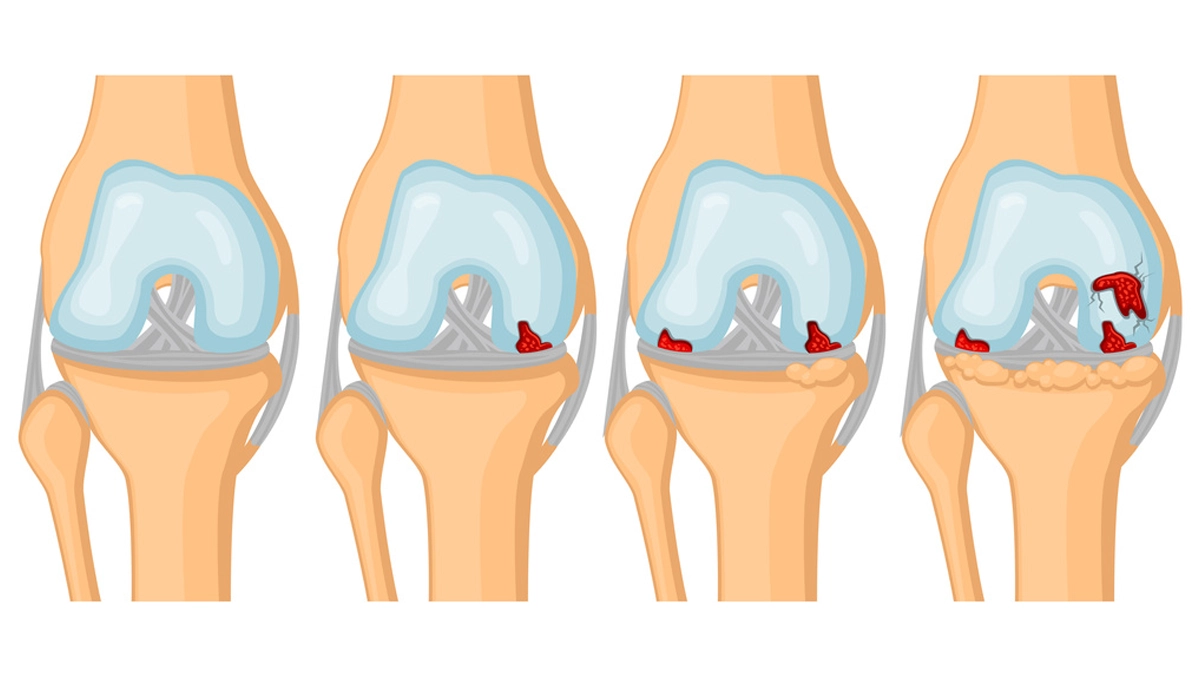

Diz Eklemi kireçlenmesi Nedir? Diz kireçlenmesi (gonartroz), uyluk kemiği (femur), kaval kemiği (tibia) ve diz kapağı (patella) arasındaki eklem yüzeylerini örten hyalin kıkırdağın yapısal bütünlüğünü kaybetmesi, alttaki subkondral kemiğin sertleşmesi (skleroz), kenarlarda osteofit (kemiksi çıkıntı) oluşması ve sinovyal zarın dönemsel irritasyonu ile seyreden dejeneratif bir eklem hastalığıdır. Sağlıklı kıkırdak, su ve proteoglikanlardan zengin esnek matrisi sayesinde düşük sürtünme ve şok emicilik sunar. Gonartrozda bu denge bozulur; kıkırdak su tutma kapasitesini ve düz yüzey yapısını yitirir, mikroçatlaklarla pürüzlenir. Yük artık geniş yüzeye değil daha dar temas noktalarına biner; bu da her adımda basınç tepe noktalarını yükseltir, ağrı ve hareket kısıtlılığına zemin hazırlar.

Süreç yalnız kıkırdağa indirgenemez. Kıkırdağın altında yer alan subkondral kemik, artan yükleri karşılamak için kalınlaşıp sertleşir; bu bir süre ağrıyı tamponlasa da zamanla eklem uyumunu bozar. Eklemin kenarlarında gelişen osteofitler, vücudun yükü dağıtma çabasıdır; fakat hareket açıklığını daraltabilir ve mekanik takılma/krepitasyon hissini artırabilir. Sinovyum (eklemi döşeyen zar), dökülen kıkırdak parçacıklarına ve biyokimyasal değişime iltihabi bir yanıt verir; dizde ısınma, şişlik ve dolgunluk dönemleri (alevlenme) bu nedenle ortaya çıkar. Bu alevlenmeler, birçok kişinin “bazı günler çok iyi, bazı günler çok kötü” diye tarif ettiği dalgalı seyri açıklar.

Gonartroz çok etkenli bir tablodur. Yaşla birlikte kondrositlerin (kıkırdak hücreleri) onarım kapasitesi azalır; kollajen ağı gevşer, proteoglikan içerik düşer. Ancak biyomekanik yüklenme paternleri ve kas–sinir kontrolü en az bu kadar belirleyicidir. Diz yalnızca menteşe gibi bükülüp açılmaz; aynı zamanda küçük rotasyon bileşenleri vardır. Varus (içe kapanma) eğiliminde yük medial bölmeye, valgus eğiliminde lateral bölmeye yoğunlaşır ve zamanla ilgili bölmede kıkırdak aşınması hızlanır. Patellofemoral eklem (diz önü) tutulumunda ise merdiven, çömelme, eğilip doğrulma sırasında ön diz ağrısı ve krepitasyon belirgindir. Kısacası diz kireçlenmesi, eklem geometrisi–kas gücü–yürüyüş paterninin ortak ürünüdür.